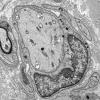

PERIPHERAL NEUROPATHY

7B CIDP (11)